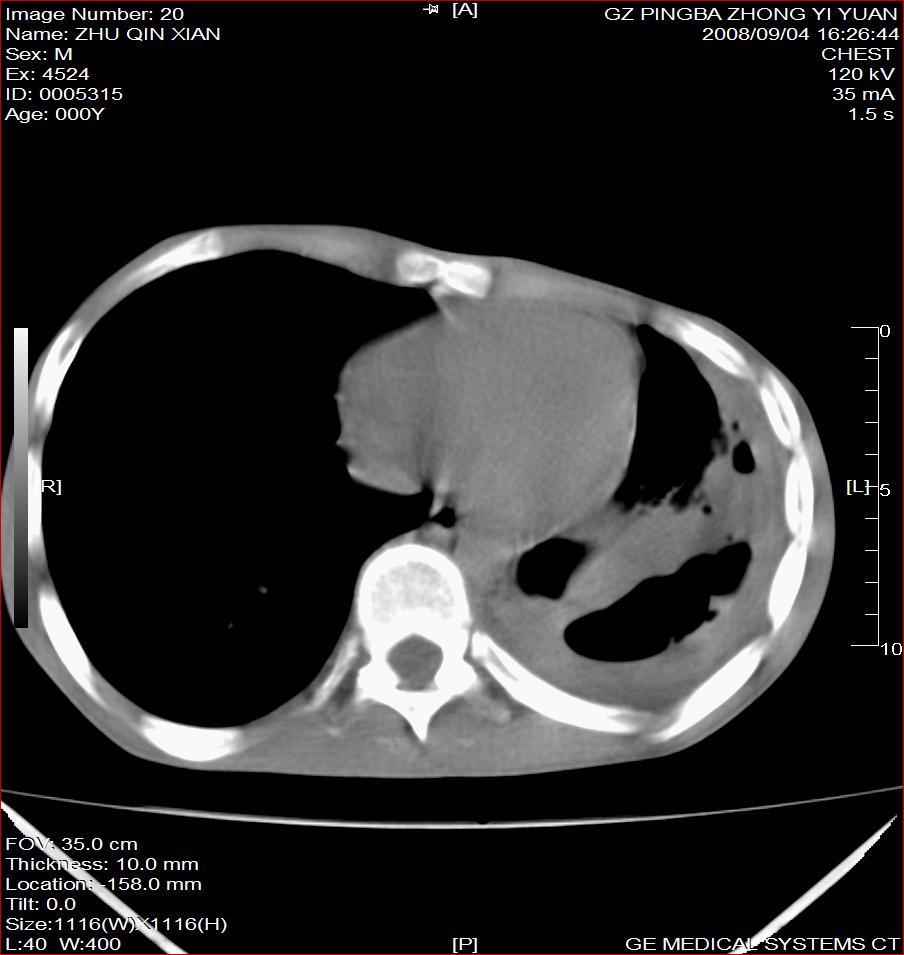

以下是引用随光逐影在2008-9-4 20:05:00的发言:[br]1)考虑两肺结核。2)左侧胸膜炎(胸膜肥厚、粘连,胸腔积液)。3)左侧局限性气胸。

以下是引用子十在2008-9-4 19:34:00的发言:[br]左上肺结核并空洞及双肺播散。节段性肺不张、胸腔积液、胸膜肥厚粘连。[br]